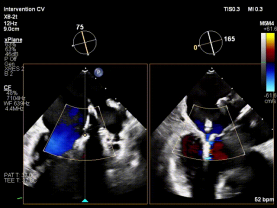

红区脱垂(DMR):复杂解剖下的精准修复

病例1为典型退行性二尖瓣脱垂(DMR),术前超声提示外交界瓣叶明显脱垂,反流程度达重度(4+),伴随活动后气促等心衰症状。由于病变位于“红区”,瓣叶结构复杂、对合不稳定,属于TEER治疗中的高难度类型。